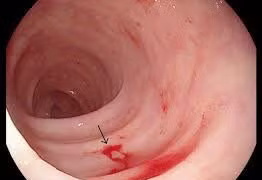

(khoahocdoisong.vn) - Chảy máu do loét dạ dày tá tràng là một cấp cứu thường gặp chiếm 40 – 45% trong chảy máu đường tiêu hóa trên. Bệnh hay gặp ở bệnh nhân trên 50 tuổi, có tiền sử loét dạ dày tá tràng nhiều năm, chảy máu nhiều lần gặp nhiều ở những bệnh nhân có nhóm máu O...